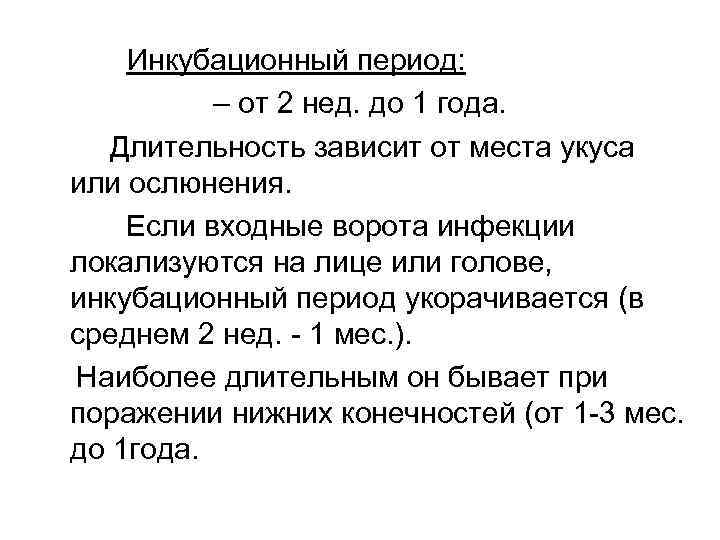

Инкубационный период: – от 2 нед. до 1 года. Длительность зависит от места укуса или ослюнения. Если входные ворота инфекции локализуются на лице или голове, инкубационный период укорачивается (в среднем 2 нед. - 1 мес. ). Наиболее длительным он бывает при поражении нижних конечностей (от 1 -3 мес. до 1 года.